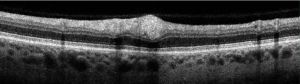

Diagnosis is usually made following a complete ocular examination, including a detailed dilated fundus exam. However, fluorescein angiography may reveal areas of capillary nonperfusion adjacent to cotton-wool spots.[1] Additional workup may be needed to detect the underlying etiology. On optical coherence tomography (OCT), cotton-wool spots can appear as focal or segmental areas of thickening, with hyperreflectivity of the inner retinal layers in the acute phase. This thickening may be mostly confined to the nerve fiber layer with sparing of the outer retinal layers, consistent with the postulation of axoplasmic debris accumulation within the ganglion cell axons that correlate to clinically apparent cotton-wool spots.[9] During resolution, these lesions can progress to inner retinal thinning or atrophy, or may in some cases result in cystic changes. Optical coherence tomography has been used to monitor the progression, extent, and resolution of cotton-wool spots.